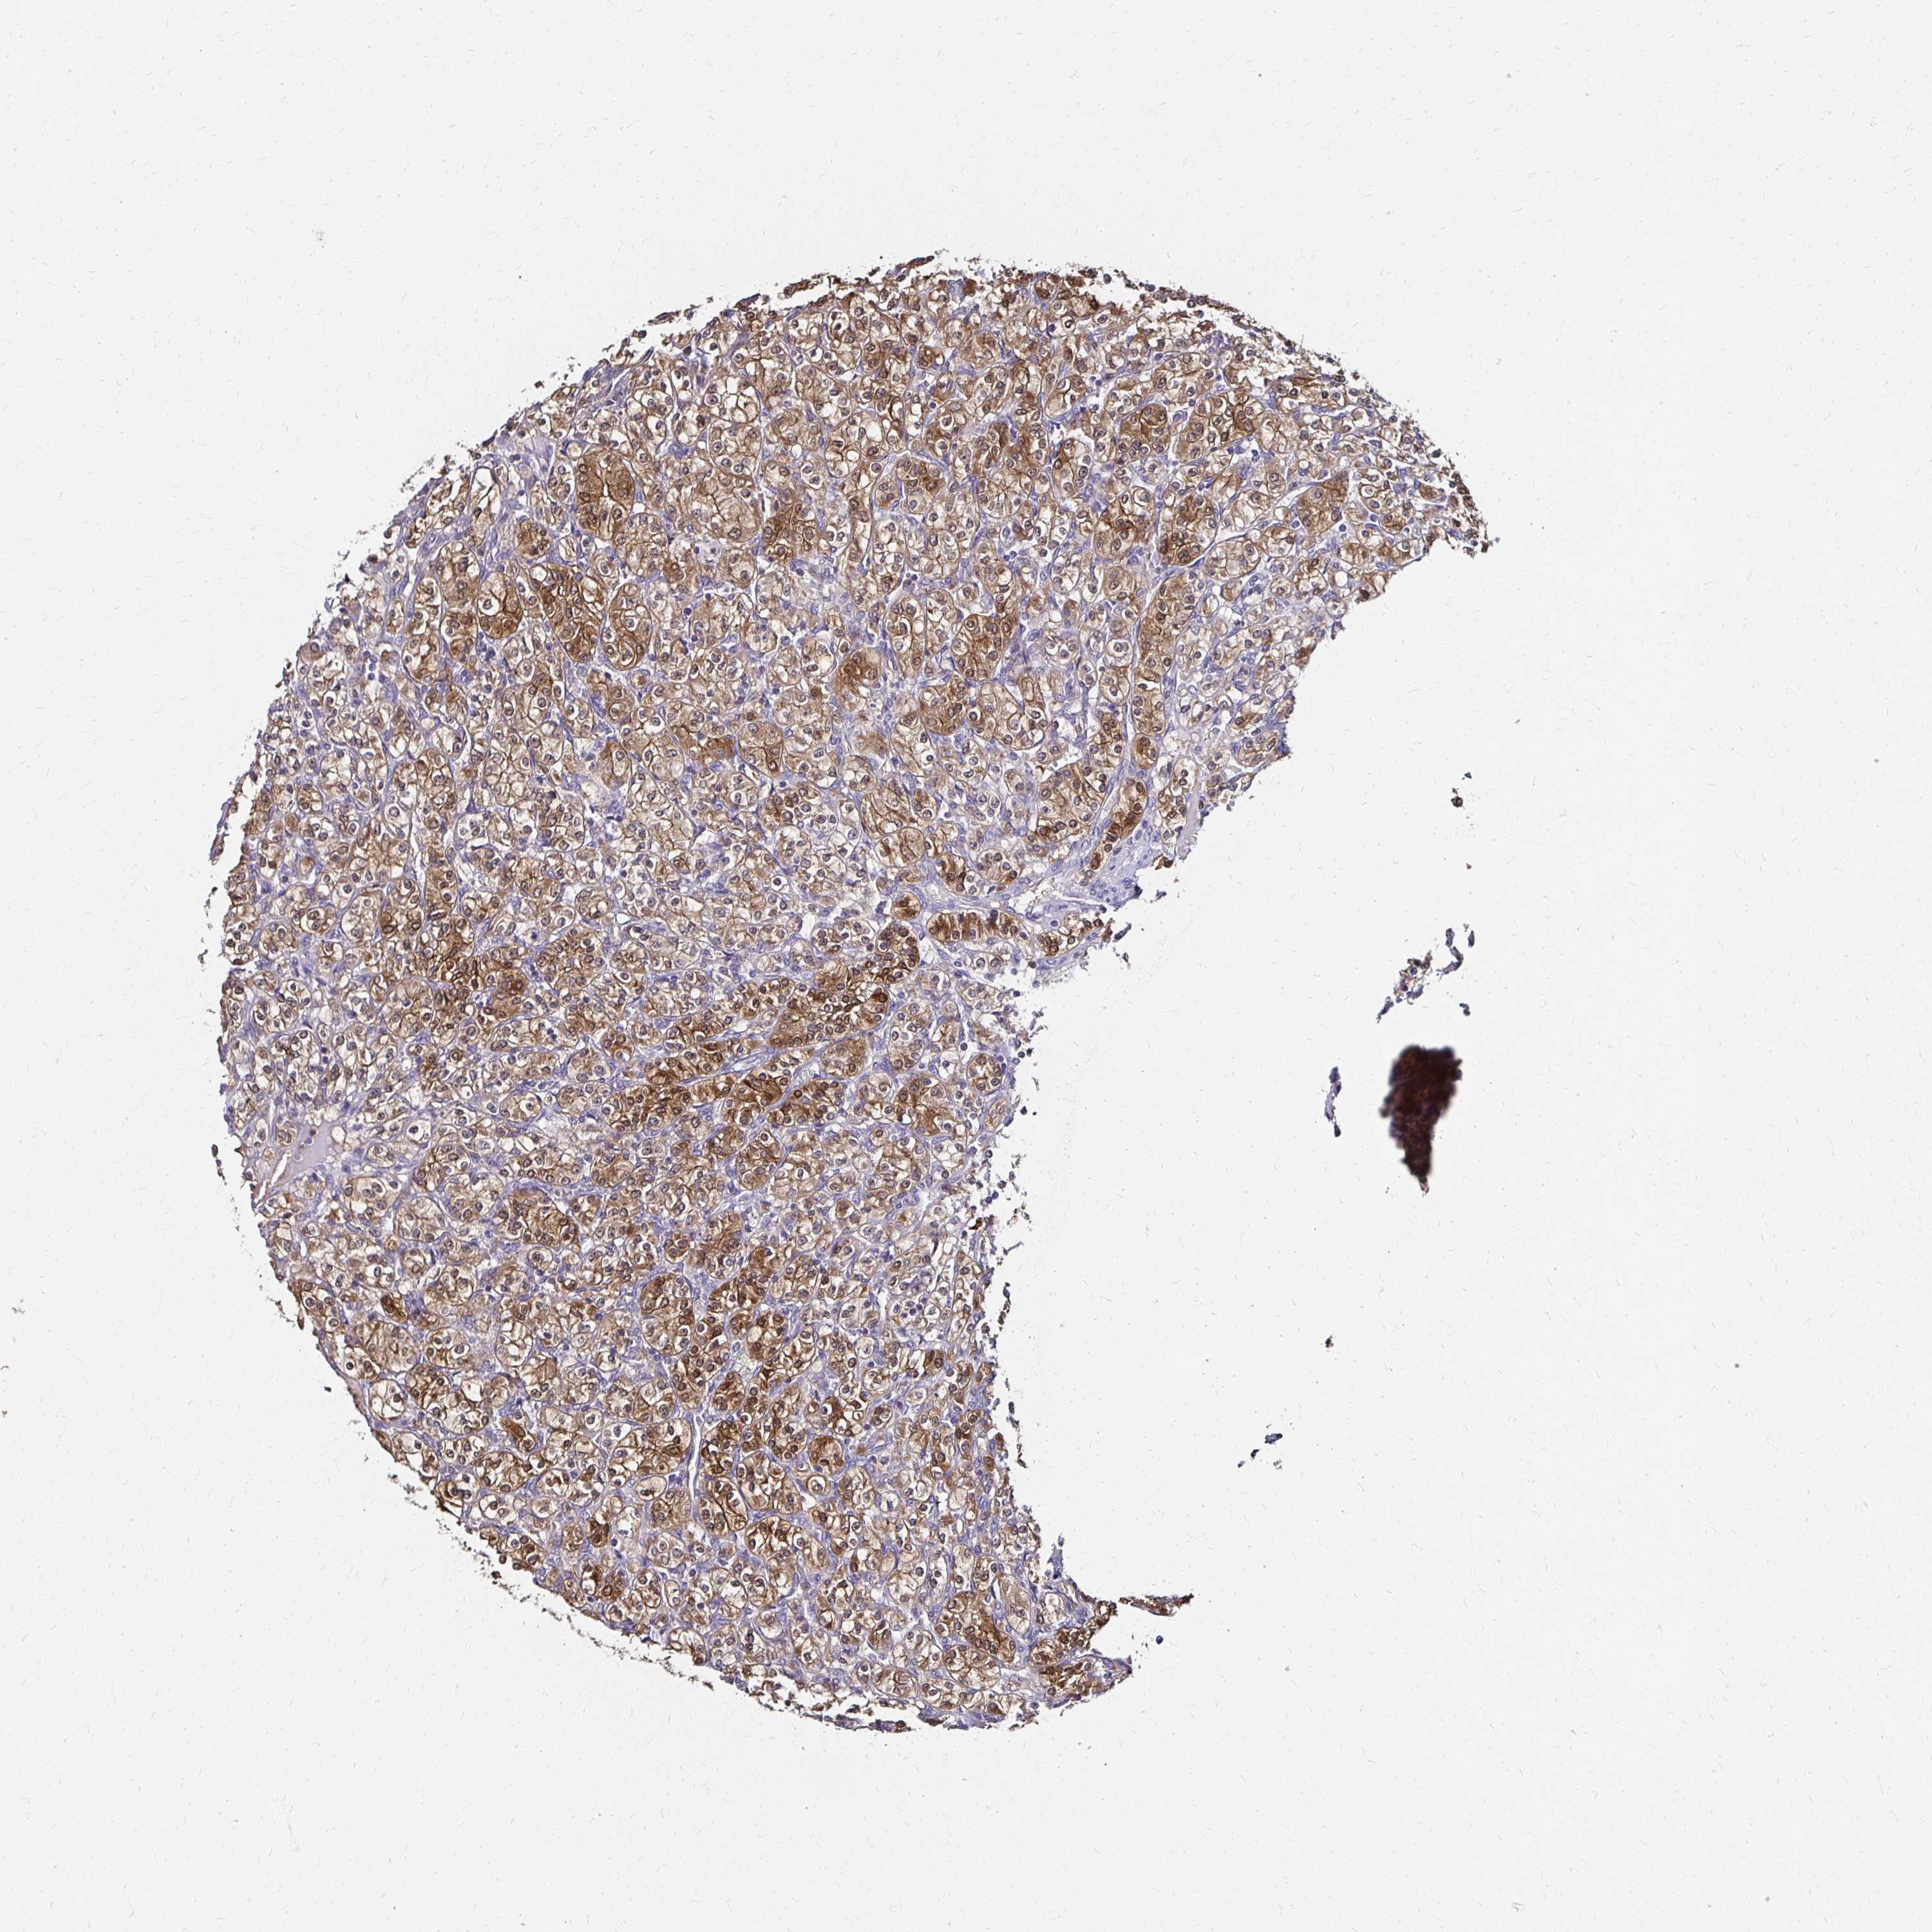

KIDNEY RENAL CLEAR CELL CARCINOMA (TCGA) - Interactive survival scatter ploti

The Survival Scatter plot shows the clinical status (i.e. dead or alive) for all individuals in the patient cohort, based on the same data that underlies the corresponding Kaplan-Meier plots. Patients that are alive at last time for follow-up are shown in blue and patients who have died during the study are shown in red.

The x-axis shows the expression levels (FPKM) of the investigated gene in the tumor tissue at the time of diagnosis. The y-axis shows the follow-up time after diagnosis (years). Both axes are complimented with kernel density curves demonstrating the data density over the axes. The top density plot shows the expression levels (FPKM) distribution among dead (red) and alive patients (blue). The right density plot shows the data density of the survived years of dead patients with high and low expression levels respectively, stratified using the cutoff indicated by the vertical dashed line through the Survival Scatter plot. This cutoff is automatically defined based on the FPKM cutoff that minimizes the p-score. The cutoff can be changed by dragging the vertical line or by entering a cutoff value in the square labeled "Current cut-off".

Under the Survival Scatter plot the p-score landscape (black curve; left axis) is shown together with dead median separation (red curve; right axis). Dead median separation is the difference in median mRNA expression between patients who have died with high and low expression, respectively. It is calculated as follows: median FPKM expression of dead patients with high expression - median FPKM expression of dead patients with low expression. This is intended to aid the user in visually exploring custom cutoffs and the associated p-scores and dead median separation.

Individual patient data is displayed and can be filtered by clicking on one or more of the category buttons on the top of the page. Categories describing expression level and patient information include: high, low, alive, dead, female, male and tumor stages. The scale of the x-axis can be toggled between linear and log-scale by clicking on the "x log" button. Mouse-over function shows TCGA ID, patient information and mRNA expression (FPKM) for each patient.

& Survival analysisi

Kaplan-Meier plots summarize results from analysis of correlation between mRNA expression level and patient survival. Patients were divided based on level of expression into one of the two groups "low" (under cut off) or "high" (over cut off). X-axis shows time for survival (years) and y-axis shows the probability of survival, where 1.0 corresponds to 100 percent.

TXN is not prognostic in Kidney Renal Clear Cell Carcinoma (TCGA)

Best expression cut offi

Based on the FPKM value of each gene, patients were classified into two groups and association between prognosis (survival) and gene expression (FPKM) was examined. The best expression cut-off refers the FPKM value that yields maximal difference with regard to survival between the two groups at the lowest log-rank P-value. Best expression cut-off was selected based on survival analysis .

When clicking on this number, the vertical dashed line indicating cut-off, the interactive survival plot, and the Kaplan-Meier curve will be adjusted to show results based on the best expression cut-off.

: 200.99

Median expressioni

Median expression refers to the median FPKM value calculated based on the gene expression (FPKM) data from all patients in this dataset. When clicking on this number, the vertical dashed line indicating cut-off, the interactive survival plot, and the Kaplan-Meier curve will be adjusted to show results based on the median expression.

: N/A

Median follow up timei

Median follow up time refers to the median time (years) after diagnosis with this type of cancer, based on clinical data from all patients in this dataset.

P scorei

Log-rank P value for Kaplan-Meier plot showing results from analysis of correlation between mRNA expression level and patient survival.

N/A

5-year survival highi

5-year survival for patients with higher expression than the expression cutoff.

For melanoma and glioma, 3-year survival is shown.

5-year survival lowi

5-year survival for patients with lower expression than the expression cutoff.

TCGA RNA samplesi

RNA-seq data is reported as average FPKM (number Fragments Per Kilobase of exon per Million reads), generated by the The Cancer Genome Atlas (TCGA) .

Normal distribution across the dataset is visualized with box plots, shown as median and 25th and 75th percentiles. Points are displayed as outliers if they are above or below 1.5 times the interquartile range. FPKM values of the individual samples are presented next to the box plot.

Average pTPM 293.6

Number of samples 521